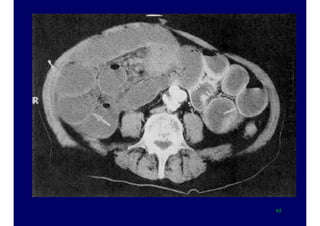

Severity is assessed by CT and contrast enhanced CT

Severity is assessedby CT and contrast enhanced CT 38